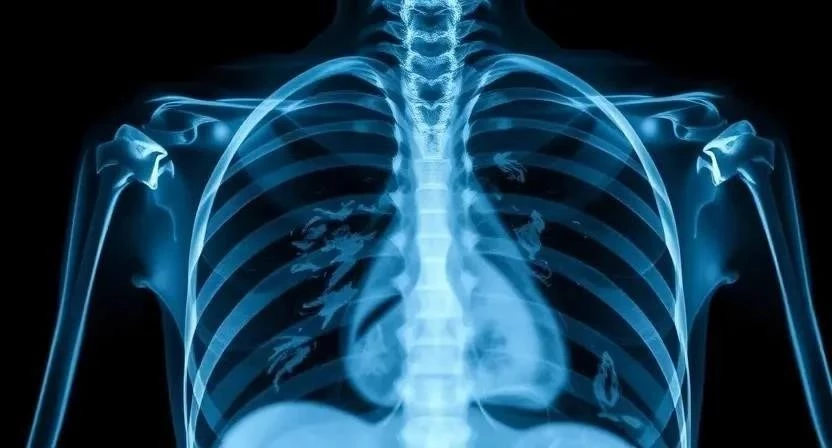

Диагностика пневмонии обычно включает в себя физический осмотр, рентген грудной клетки и анализы крови. Рентген грудной клетки позволяет выявить наличие воспаления в легких. Анализы крови помогают определить тип инфекции (бактериальная или вирусная) и оценить общее состояние организма. В некоторых случаях может потребоваться посев мокроты для определения конкретного возбудителя инфекции. Интерпретация результатов рентгена требует опыта, так как некоторые изменения могут быть вызваны другими заболеваниями. Я помню, как врач внимательно изучал мой рентгеновский снимок, чтобы точно определить степень поражения легких. Важно понимать, что самодиагностика недопустима, и при подозрении на пневмонию необходимо обратиться к врачу.